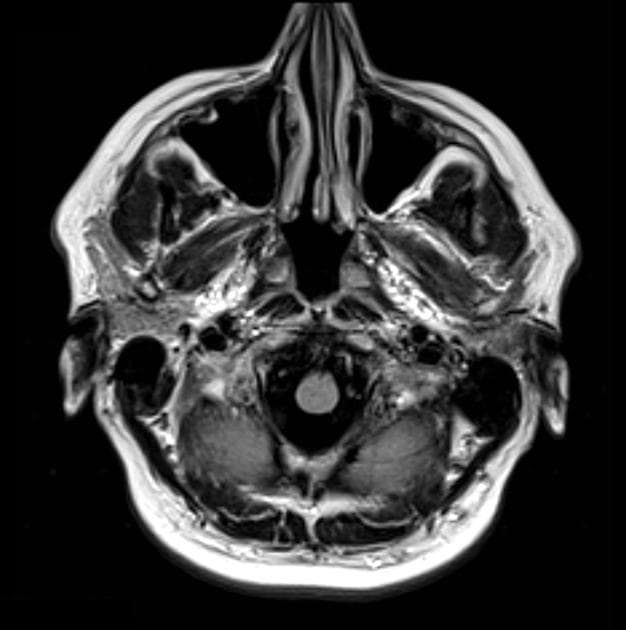

- Chụp cộng hưởng từ (MRI) sọ não cho thấy một khối dạng đặc, tăng quang mạnh ở vùng trung tuyến tại vùng trên yên/giá của não thất ba, kích thước khoảng 15 x 17 x 21 mm. Vị trí giá của não thất ba được ưu tiên hơn do khối này làm đầy ngách thị và đẩy các thể nhục xuống phía dưới.

- Trên hình ảnh T2 cắt ngang, khối làm tách rộng và đẩy xuống dưới các đường dẫn thị giác, củng cố thêm vị trí khối u tại giá não thất ba.

- Khối có khuếch tán thuận lợi (facilitated diffusion).

- Cuống nối yên (infundibulum) được thấy nằm dưới tổn thương, kéo dài xuống đến một tuyến yên (pituitary gland) bình thường.

- Hố yên (sella turcica) không có gì bất thường.

- Không thấy thành phần mỡ hoặc dạng nang trong khối.